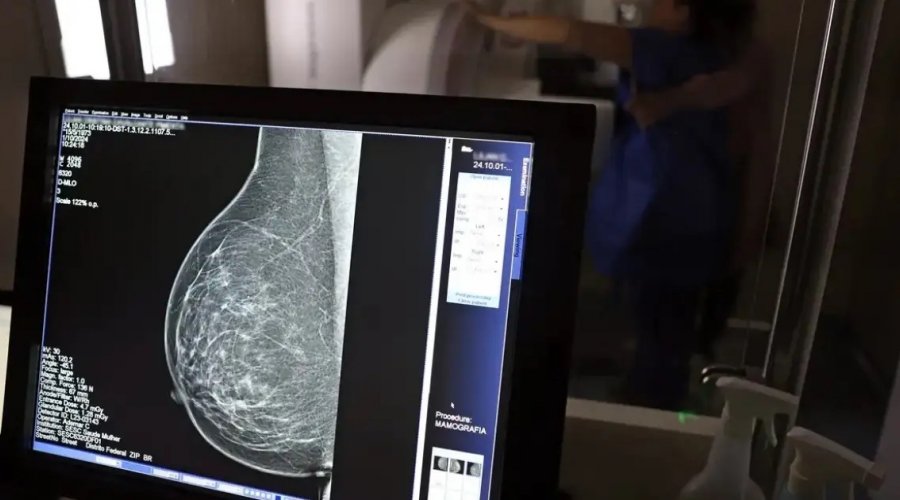

Foto: José Cruz / Agência Brasil

O Ministério da Saúde anunciou, nesta terça-feira (23), uma atualização nas diretrizes para rastreamento do câncer de mama no SUS. Agora, mulheres de 40 a 49 anos poderão realizar mamografias mesmo sem sintomas da doença. A decisão leva em conta que essa faixa etária concentra 23% dos casos e que a identificação precoce aumenta as chances de tratamento bem-sucedido.

Até então, o exame era indicado rotineiramente apenas para mulheres a partir dos 50 anos. Com a nova recomendação, o procedimento deverá ser solicitado em conjunto com o profissional de saúde, que orientará sobre riscos e benefícios.

Em 2024, o SUS já havia realizado mais de 1 milhão de mamografias em mulheres com menos de 50 anos, representando 30% do total de exames. Outra mudança anunciada foi a ampliação da faixa etária máxima para rastreamento preventivo, que passou de 69 para 74 anos. Dados do ministério mostram que 60% dos diagnósticos acontecem entre 50 e 74 anos.

Segundo a pasta, a atualização aproxima o Brasil de protocolos internacionais, como os adotados na Austrália, e reforça a meta de ampliar o diagnóstico precoce de uma doença que, apenas no último ano, registrou 37 mil novos casos no país.